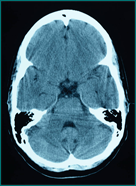

1) The body's intelligence develops the brain and spinal cord first.  This occurs within 18 days of conception.

2) The intelligence is expressed through the brain and spinal cord which are so valuable and delicate they are the only organs encased in bone.  The brain weighs approximately three pounds and is covered by the skull.  Twenty-four moveable vertebrae protect the small, slender spinal cord which is about the thickness of a pencil.

The Communication Center:

Gray's Anatomy tells us the central nervous system controls and coordinates ever cell, tissue, muscle, and organ.  How does is do this?

The intelligence expressed through the central nervous system continually sends vitally important messages between your brain and body which travels through the central nervous system at a rate of 325mph through 45 miles of your nerves!